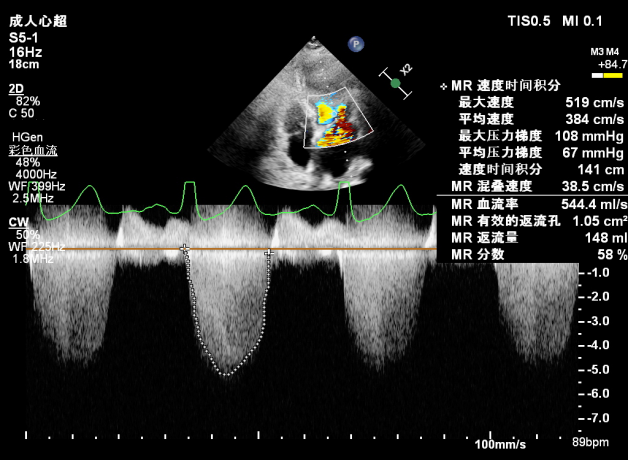

PISA法定量EROA:1.05cm²,Rvol:148ml,RF:58%。

肺静脉血流频谱呈收缩期反向